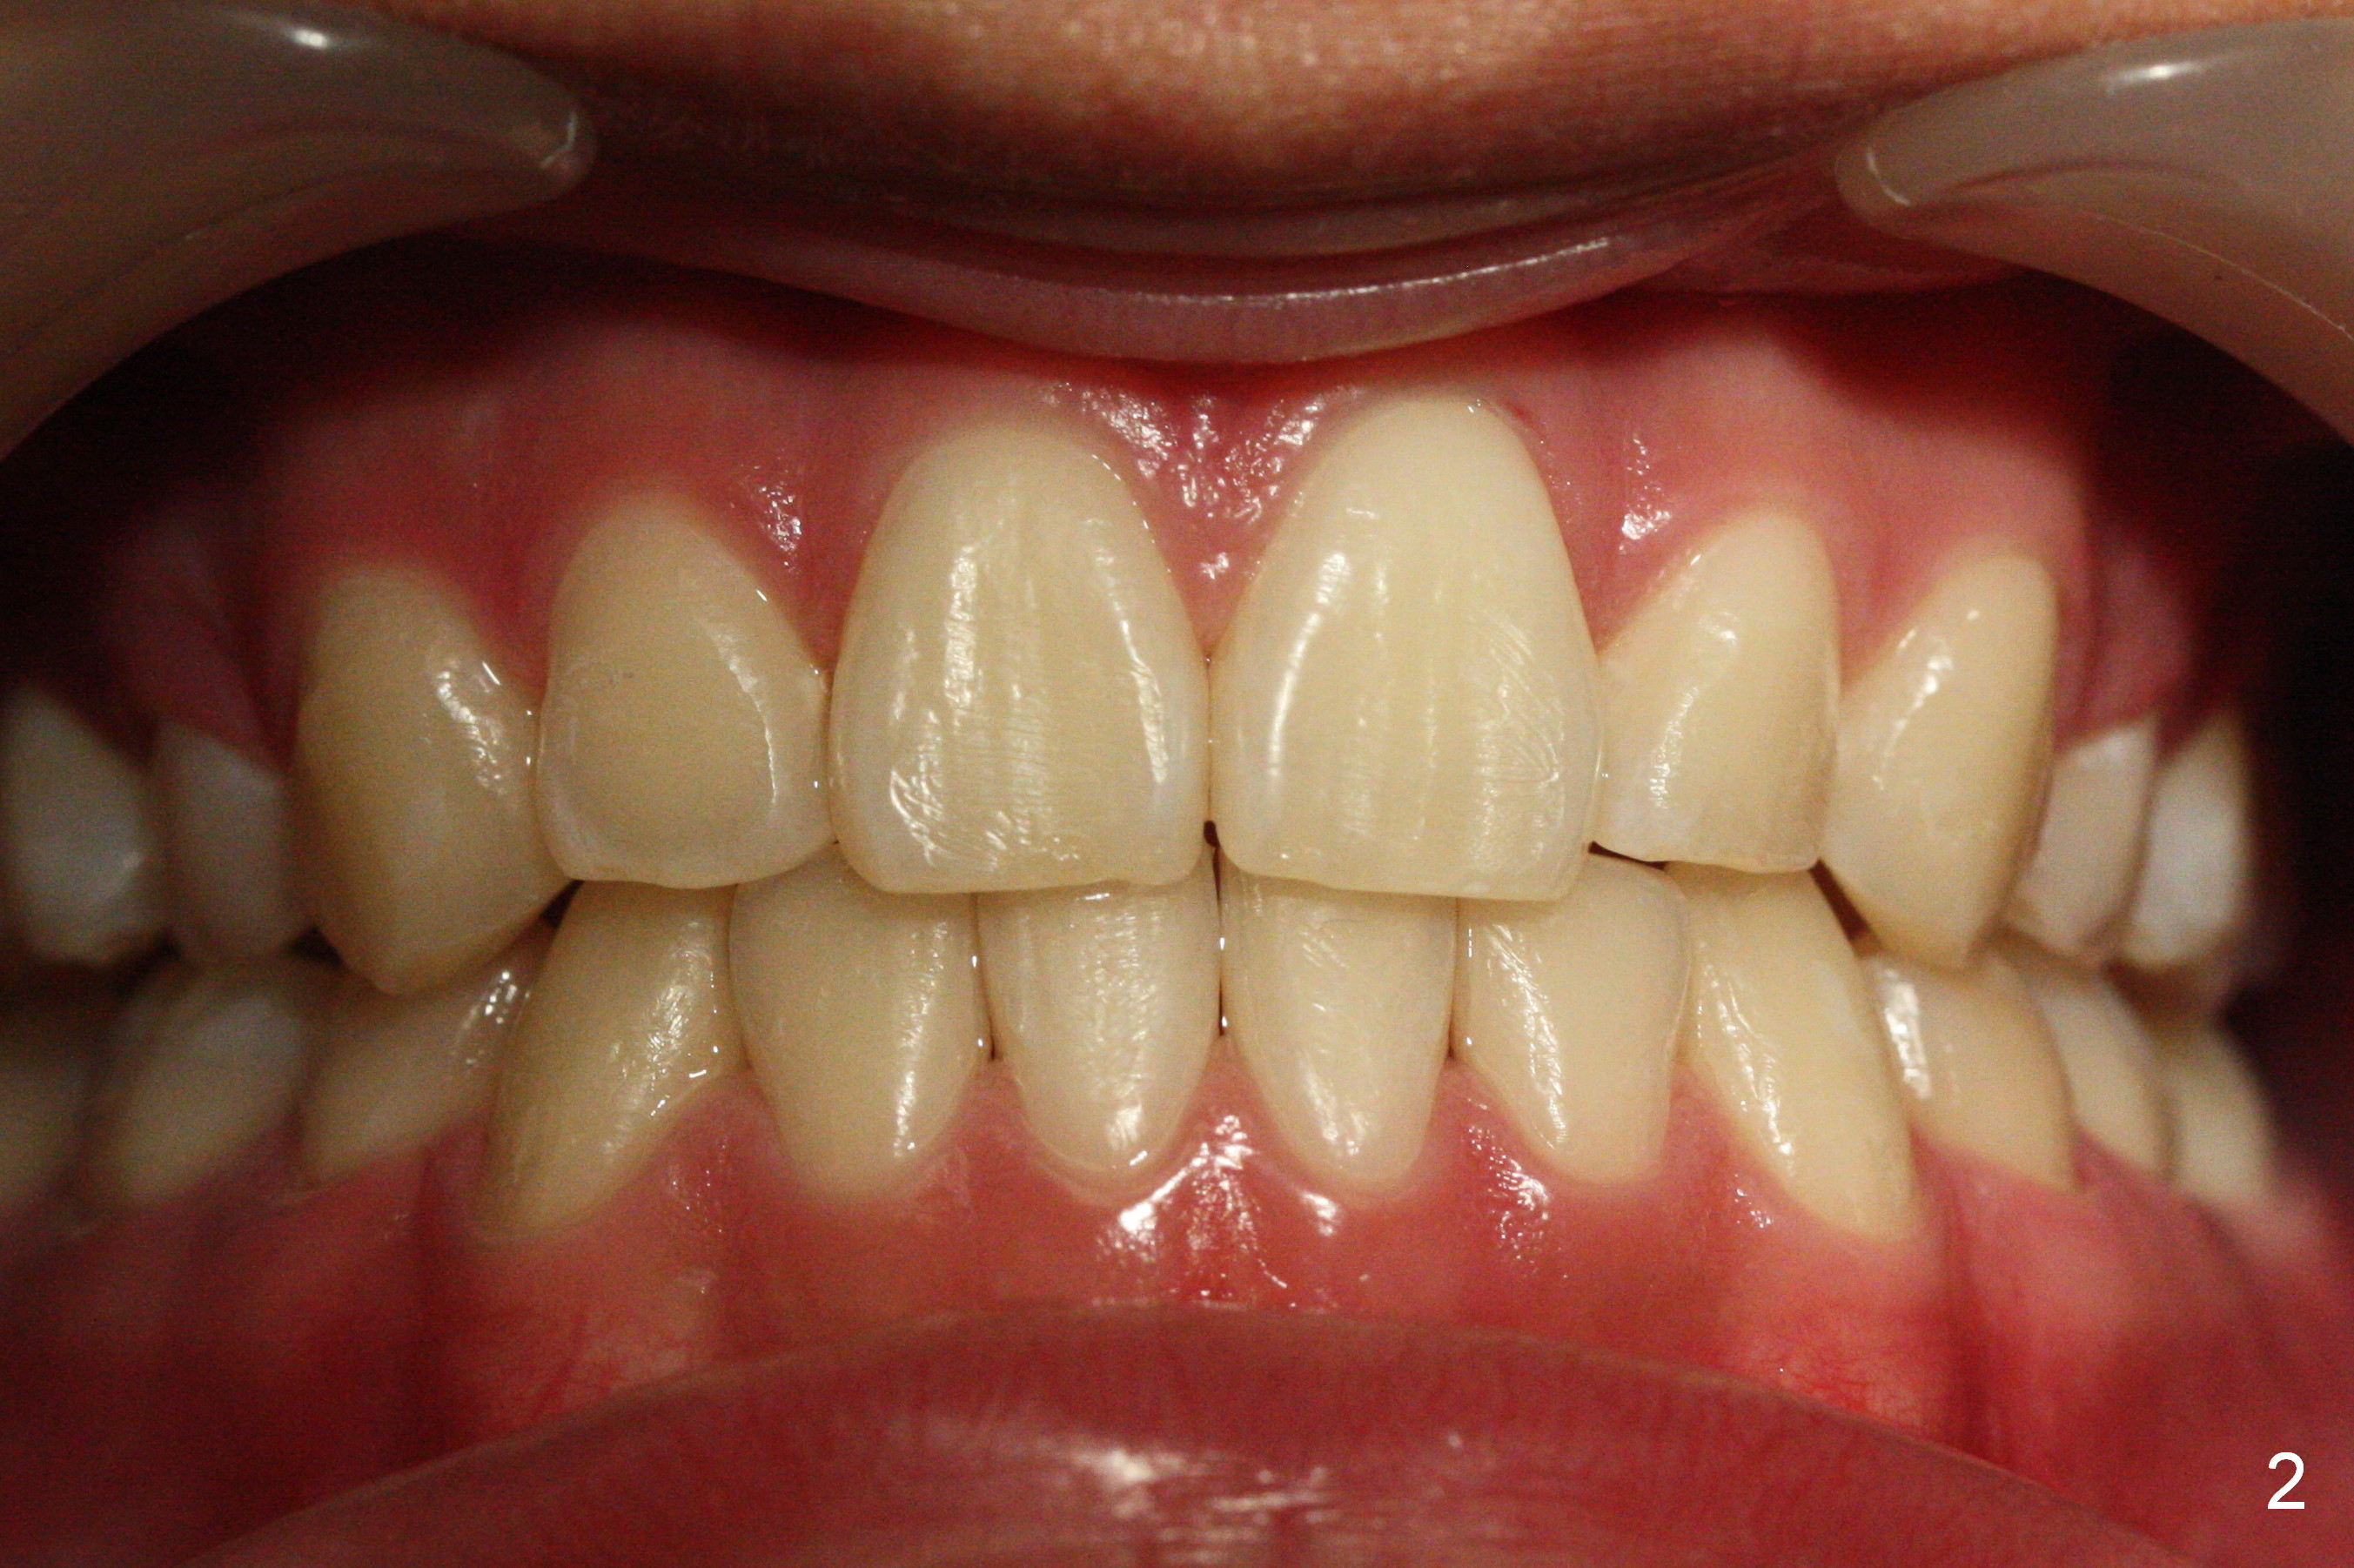

How to Take Before and After Photos for Orthodontics

First of all, before & after photos should include face, which provides evidence that after treatment (extraction) the facial profile improves.

Lighting should be double checked (Fig.1,2).